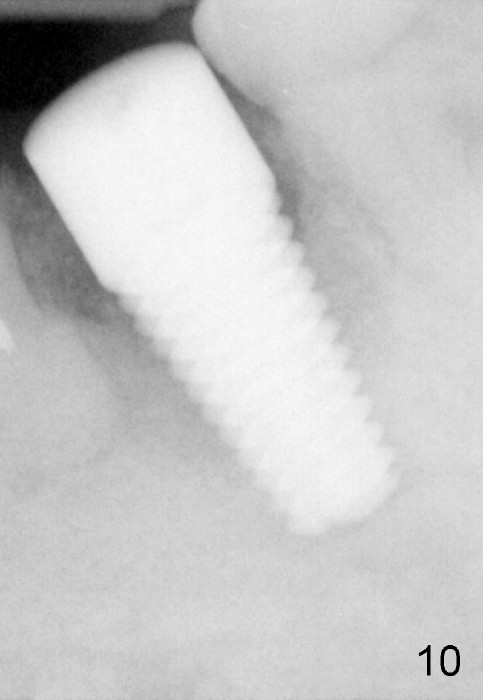

Three months postop, the buccal fistula disappear (Fig.11). But the implant has mild mobility, as evidenced by a narrow band of radiolucency immediately around the apical portion of the implant (Fig.10).